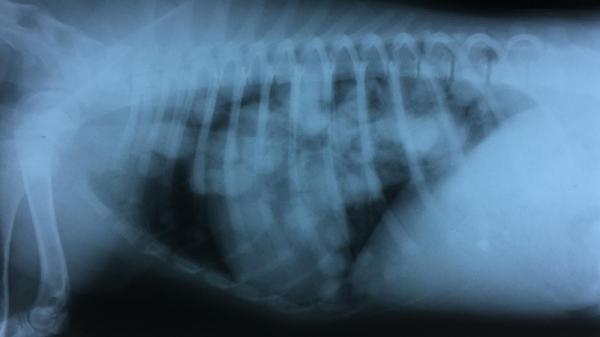

Tipos de tumores óseos en perros

Pueden ser tanto malignos como benignos. Entre los primeros, como hemos dicho, destaca el osteosarcoma, que puede aparecer a cualquier edad y con mayor predisposición en perros grandes. Estos tipos de tumores en perros se presentan más frecuentemente en las patas delanteras, pero también pueden afectar a las traseras, las costillas o la mandíbula. Como síntomas de tumores en perros de este tipo, podemos ver que el perro cojea y la pata se hincha de una manera dolorosa. Suelen extenderse a los pulmones.

Por otro lado, dentro de los tumores óseos benignos están los osteomas, en cabeza y cara, y los osteocondromas, que afectan a perros jóvenes en costillas, vértebras, extremidades, etc.

Tanto en este caso como en el resto de tumores en perros, para el diagnóstico se realizarán pruebas como las analíticas de sangre, las ecografías, radiografías o tomografías computerizadas. La biopsia puede confirmar el diagnóstico.

Rescate un perrito el cual noté respiraba mal lo atendieron y tiene metastasis pulmonar y tórax según el vet asombrado de dicho caso al ser un bb de 4 meses consultaron con otros profesionales y nunca habían visto ahora le van a hacer una Eco guiada para pulsiones y extraer líquido para confirmar q tumor es